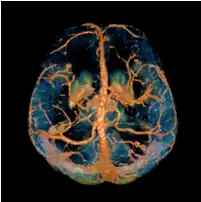

Quantitative susceptibility mapping (QSM) provides a novel contrast mechanism in magnetic resonance imaging (MRI) different from traditional susceptibility weighted imaging.[1][2][3][4][5]

The voxel intensity in QSM is linearly proportional to the underlying tissue apparent magnetic susceptibility, which is useful for chemical identification and quantification of specific biomarkers including iron, calcium, gadolinium, and super paramagnetic iron oxide (SPIO) nano-particles. QSM utilizes phase images, solves the magnetic field to susceptibility source inverse problem, and generates a three-dimensional susceptibility distribution. Due to its quantitative nature and sensitivity to certain kinds of material, potential QSM applications include standardized quantitative stratification of cerebral microbleeds and neurodegenerative disease, accurate gadolinium quantification in contrast enhanced MRI, and direct monitoring of targeted theranostic drug biodistribution in nanomedicine.